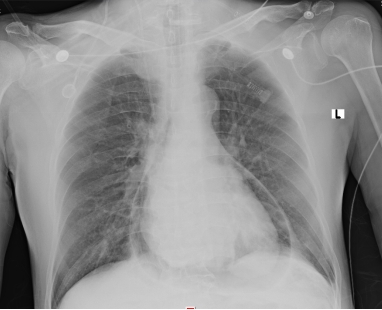

1 资料与方法患者男性,70岁,因“胸闷3 d,加重伴呼吸困难1 d”于2019年9月13日入外院。患者3 d前无明显诱因出现胸闷,伴全身乏力,夜间睡眠差(可平卧),初未予重视,1 d前胸闷加重,伴呼吸困难、运动耐量明显下降、大汗淋漓、皮肤湿冷,至外院就诊,查心电图(图 1):交界性逸搏,肢体导联低电压,Ⅰ、Ⅱ、Ⅲ、aVF、V4、V5、V6导联ST段抬高0.15 mV~0.4 mV,aVR、aVL、V1导联ST段压低0.05 mV~0.2 mV,aVL、V1导联T波倒置;心肌酶:CKMB 27.1 U/L,NT-proBNP 3 298 pg/mL。外院考虑不排除急性心肌梗死导致的心源性休克,经口气管插管接呼吸机辅助通气后为进一步诊治转入本院。患者家属否认患者有外科手术、外伤、气胸及哮喘发作史,起病以来无畏寒、高热,大、小便正常,既往1年余前因“反复咳嗽伴咳血丝痰”在外院诊断为右肺门鳞癌,合并高血压病、2型糖尿病,经依托泊苷+顺铂化疗,具体剂量不详。2019-09-07复查胸部CT提示右肺病灶较前缩小。体格检查:体温35ºC,血压86/43 mmHg,心率53次/min,呼吸15次/min(经口气管插管呼吸机辅助呼吸),神志昏迷,双侧颈静脉怒张,气管居中,桶状胸,胸廓对称,双肺呼吸动度对称,叩诊呈清音,听诊呼吸音清,双肺未闻及干湿性啰音,心前区无隆起,叩诊心界消失,心音低弱遥远,桡动脉、股动脉搏动可触及。入院后复查心电图(图 2):心房颤动,肢体导联及胸导联低电压,各导联ST-T改变较前相似,未见明显动态演变。血常规:白细胞1.27×109/L,中性粒细胞1.15×109/L,血红蛋白98 g/L,降钙素原43.01 ng/mL,超敏肌钙蛋白Ⅰ 0.048 ng/mL。急诊冠脉造影(图 3):左前降支近段轻度狭窄,中段心肌桥,收缩期重度狭窄,左回旋支远段中度狭窄,右冠中段重度狭窄,TIMI血流均为3级。患者超敏肌钙蛋白I未见明显升高,冠脉血流通畅,排除急性心肌梗死引起的ST段抬高。心脏彩超:气体干扰较大,仅能从剑突下观察,心包腔内未见积液。胸片(图 4):纵隔内可见条状透亮带,心影周围可见一弧形透亮带,考虑心包积气、纵隔气肿。入院诊断为“①心包积气、②纵隔气肿、③右肺鳞癌”,经剑突下途径行心包穿刺置管术+闭式引流术,术后液封瓶内见气体逸出,患者血压较前逐渐上升。完善胸部CT(图 5):右侧肺门增大,右主支气管与上叶支气管壁交界处见小缺损,考虑支气管破裂,心包、纵隔、胸腔及腹腔积气。纤维支气管镜(图 6)检查:可见右主支气管距隆突约1 cm处见破损,破损处周围组织呈白色,不排除癌组织浸润可能。病因考虑为右肺门鳞癌浸润右主支气管,穿孔后经纵隔与心包腔形成瘘道,引起心包积气。经过上述治疗后患者血流动力学稳定。

| 图 4 胸部正位片提示纵隔积气,心包积气 |

该例患者主要临床症状为胸闷伴有呼吸困难,体格检查时患者存在血流动力学不稳定及意识障碍,结合心电图、心肌酶结果,考虑急性心肌梗死导致心源性休克的可能,行急诊冠脉造影发现患者冠脉血流通畅,排除急性心肌梗死,同时在冠脉造影过程中发现患者心影周围存在弧形透亮带,转入ICU后行胸片检查证实心包积气的诊断。心包积气产生的原因主要为医源性操作(如心包穿刺术、胸腔穿刺术、射频消融术及埋入式起搏器植入术等)、心包炎、心包与邻近含气器官之间的瘘管形成以及外伤,其中正压通气亦是原因之一[9-12]。正压通气可迅速增加心包积气容积及加快其增长速度,从而加重心包填塞。该患者入外院后行经口气管插管接有创呼吸机辅助呼吸,本院胸部CT与支气管镜检查可见右主支气管破口,破损处周围组织呈白色,不排除癌组织浸润可能,考虑为右肺门鳞癌浸润右主支气管,穿孔后经瘘道与纵隔及心包腔相连,引起心包积气。